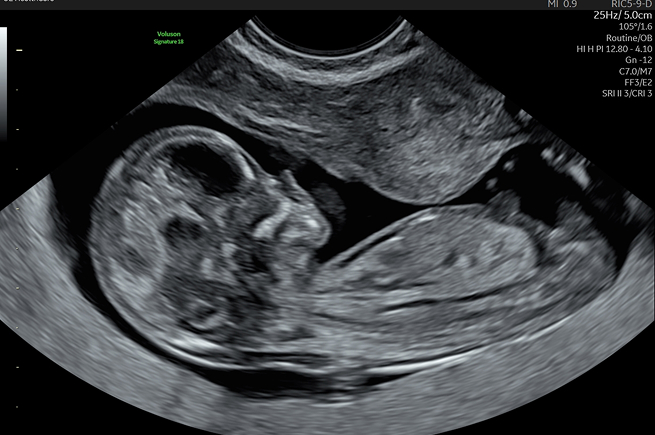

정밀 초음파

태아의 장기가 완성되는 시기에 머리부터 발끝까지 형태적 이상이 없는지 확인합니다.

뇌, 심장, 척추, 복부 장기, 손발가락 등을 세밀하게 관찰하여 태아의 건강 상태를

정확히 진단하는 매우 중요한 검사입니다.